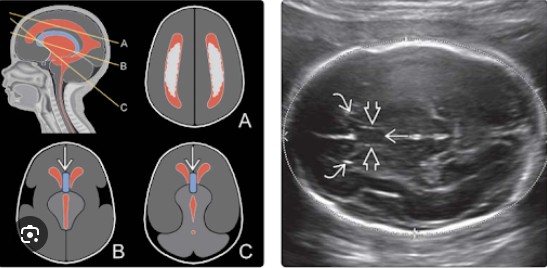

Phát hiện trên siêu âm và MRI thai

Siêu âm quý II–III: khó thấy “lá vách trong suốt” trên mặt cắt chuẩn qua đồi thị.

Não thất bên có thể gần nhau hơn.

MRI thai hỗ trợ đánh giá cấu trúc não sâu.

Cần khảo sát toàn diện để loại trừ kèm theo bất thường dải thể chai, não thất, hoặc vỏ não.